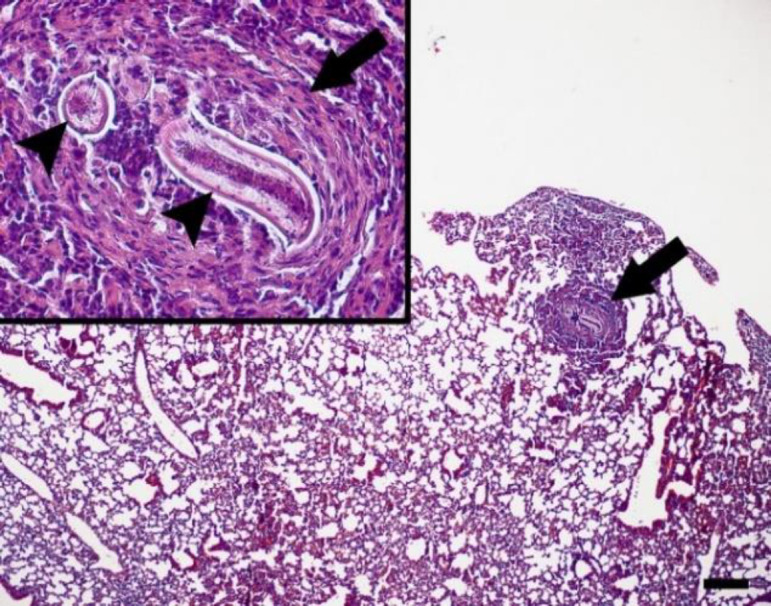

Results: T. leonina larvae were recovered from the small intestinal wall, lungs, liver, and striated muscles. No larvae were detected in the kidneys, heart, spleen, and brain using digestive or squash methods. Histological examination revealed granulomatous reactions, inflammatory cell accumulation, and larval presence in the isolated tissues. Larval concentration in the striated muscles increased over time, demonstrating the potential of Swiss albino mice to serve as paratenic hosts in toxocariasis.